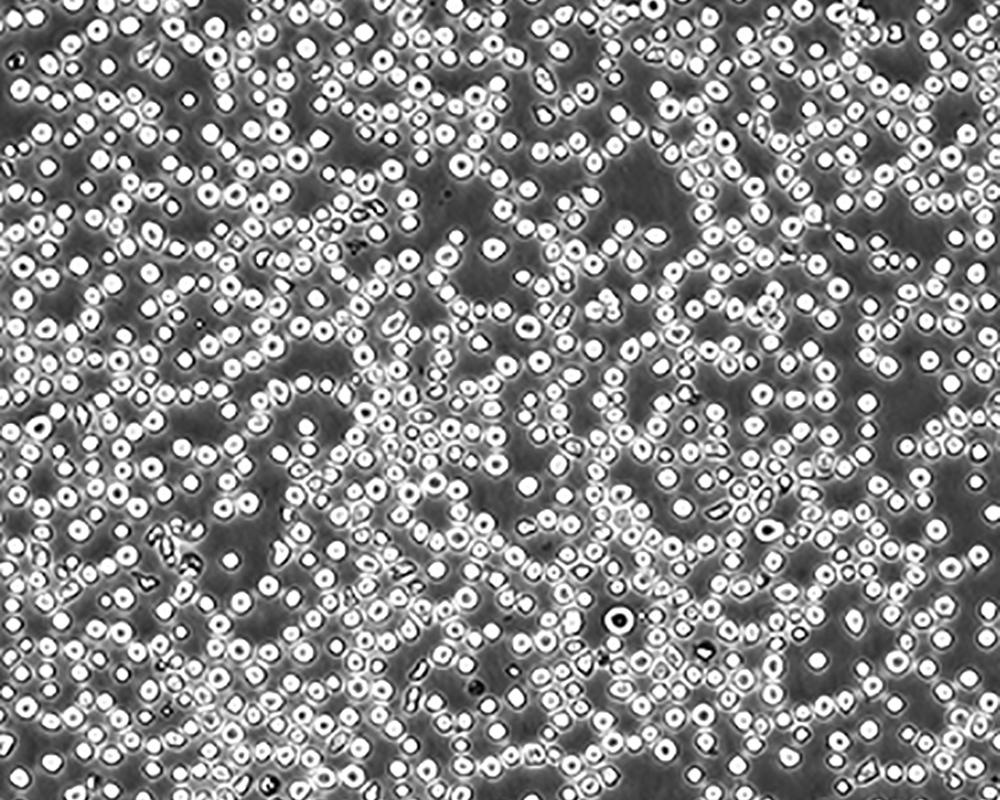

生長特性 suspension

形態(tài)特征 lymphoblast

細(xì)胞描述 CEM/C1是人T細(xì)胞白血病細(xì)胞株CCRF-CEM(見ATCC CCL-119)具有喜樹堿抗性的衍生株。1991年細(xì)胞株選擇并亞克隆了對CPT的抗性。細(xì)胞表現(xiàn)出對CPT類似物水溶性的托泊替康和非水溶性的9-氨基-CPT及10,11-亞甲二氧基-CPT具有交叉抗性。CEM/C1細(xì)胞對CPT的敏感性較母系CEM細(xì)胞低31倍。CEM/C1細(xì)胞表現(xiàn)非典型的多藥抗性和轉(zhuǎn)換拓補(bǔ)異構(gòu)酶I催化活性。對CPT的抗性維持6個(gè)月以上。